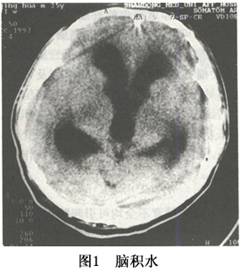

CT或MRI可確定腦室擴大及程度及皮質萎縮的程度,有時可同時瞭解引起腦積水的原因(圖1,2)。此外,CT或MRI還能瞭解腦積水是急性腦積水還是慢性腦積水,爲臨牀處理措施的應用提供依據。在腦積水的診斷中,應注意與腦萎縮引起的腦室擴大相區別,後者腦室擴大的同時可明顯地顯示出側裂或腦溝,甚至可有腦溝及腦裂的明顯擴大。另外診斷腦積水應儘可能明確是梗阻性腦積水還是交通性腦積水。